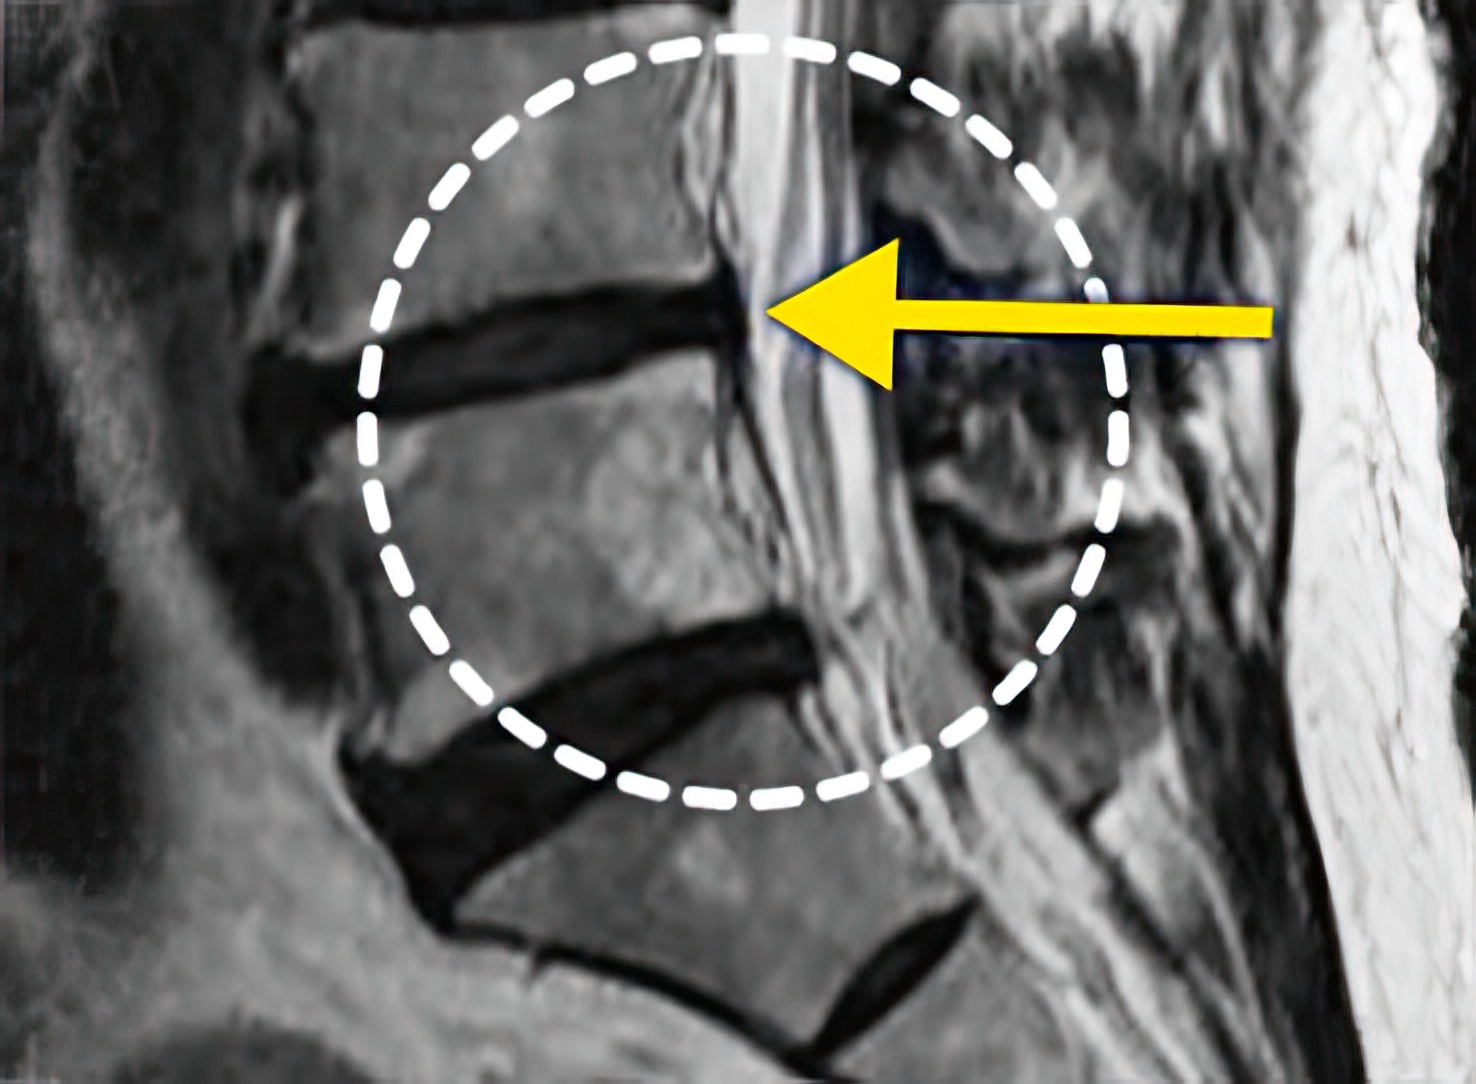

자생 비수술 한방통합치료 후

터진디스크가 흡수된 모습

Before

After

비수술 치료만으로

터진 디스크 흡수

치료 후 탈출된 디스크가

지속적으로 흡수되어 10년 후 2/3 감소